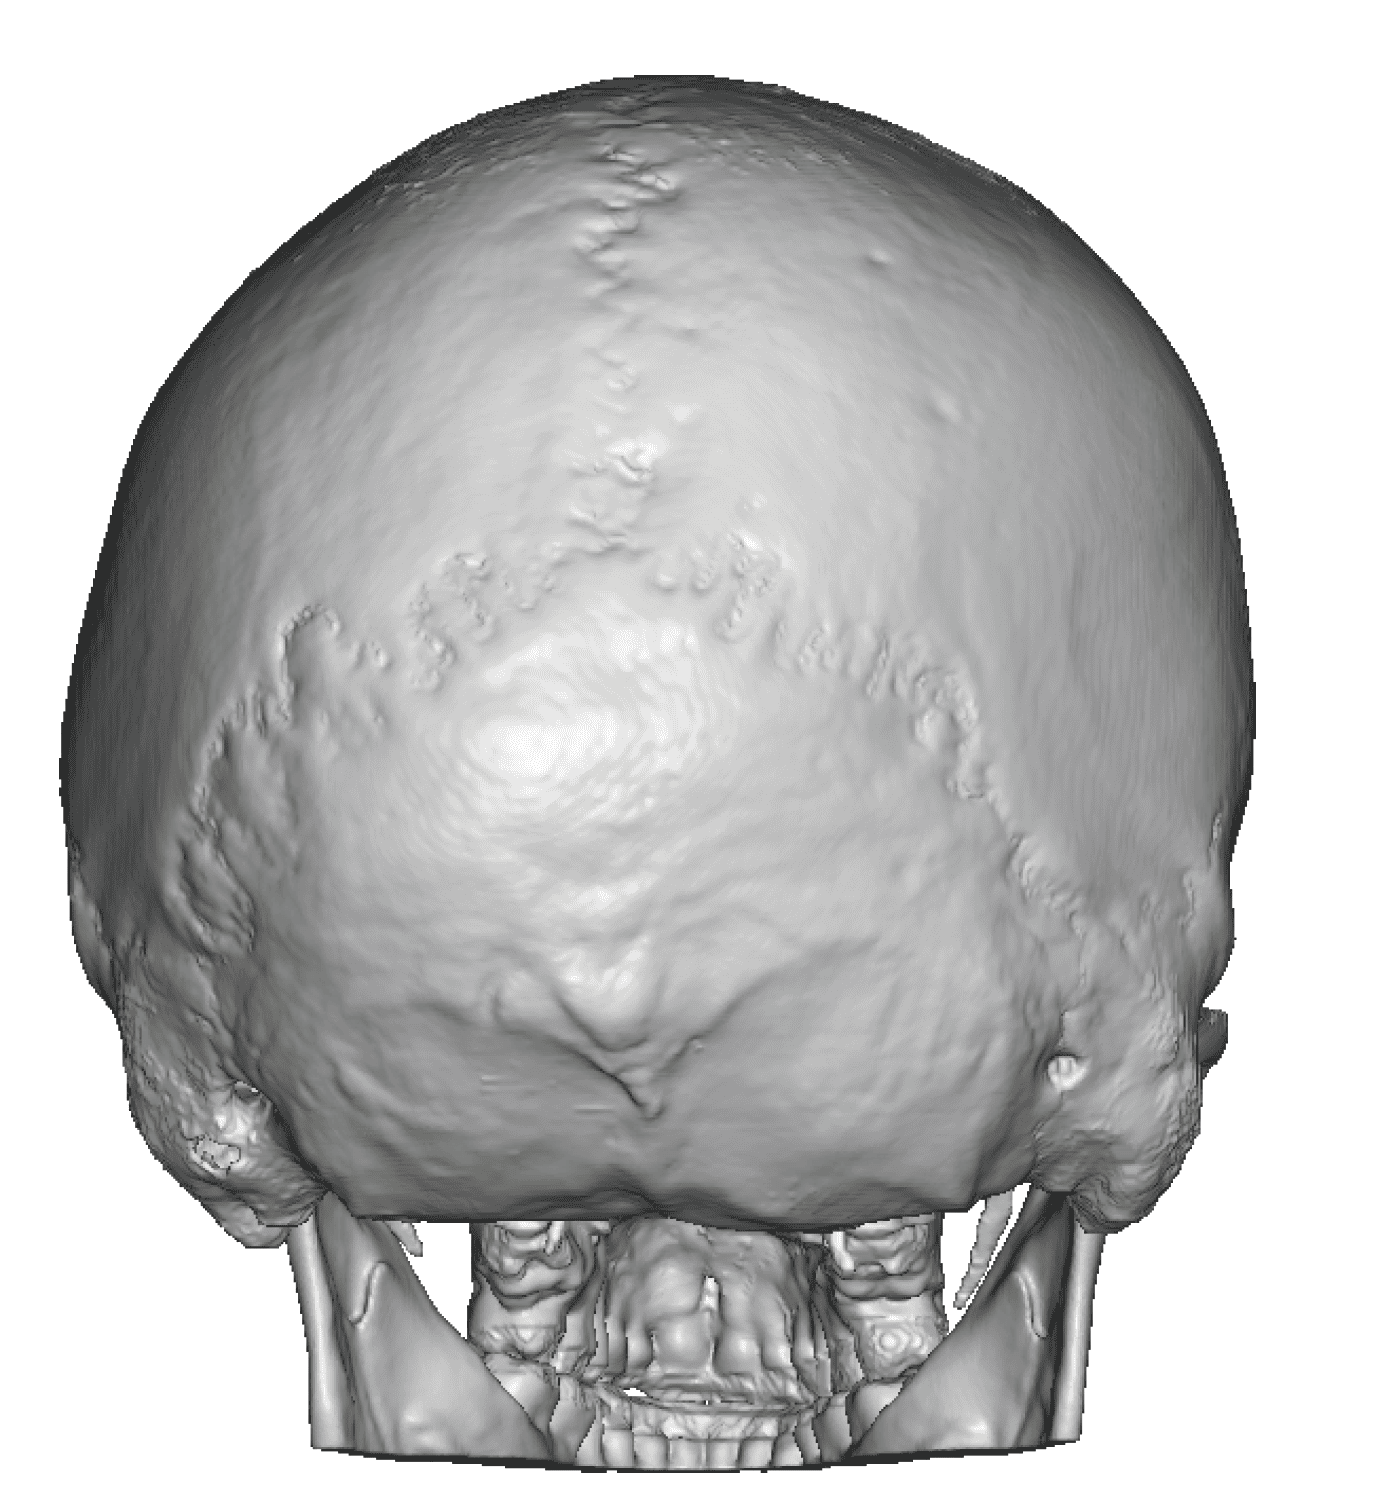

Severe narrowing skull deformity from prior sagittal craniosynostosis repair as an adult.

Complete replacement of entire skull by a custom implant with temporal fat injections.

Severe narrowing skull deformity from prior sagittal craniosynostosis repair as an adult.

Complete replacement of entire skull by a custom implant with temporal fat injections.